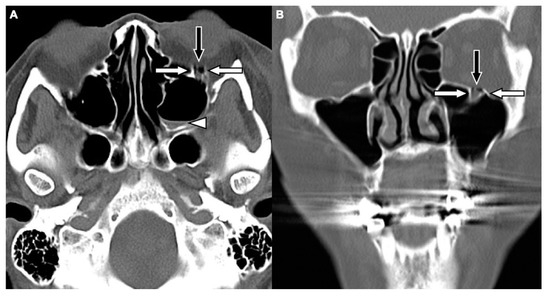

Two board-licensed radiologists (L.D.J. and Y.Y.C.) who were blinded to the patients’ clinical information reviewed only the head CT images by means of consensus. The radiologists were permitted to manipulate the window and level of the images. The CT variables related to the cranium included intracranial hemorrhage (ICH; epidural hemorrhage, subdural hemorrhage, subarachnoid hemorrhage, and intracerebral hemorrhage), and skull fractures. The CT variables related to OFFs included orbital floor discontinuity (Figure 1), gas bubbles entrapped between the floor fragments (Figure 1), inferior extraconal emphysema (Figure 2), orbital fat herniation into the maxillary sinus (Figure 2), and ipsilateral maxillary hemosinus (MHS, Figure 3). MHS was defined as high-attenuation opacity at the dependent portion of the maxillary sinus measuring ≥ 45 Hounsfield units (HU) as the lower limit of attenuation for clotted blood [15]. Since MHS is a relevant indicator used to detect OFFs on CT scans [5,16], we further classified MHS into the following three CT subtypes: (1) Type 1, high-attenuation opacity mixed with mottled gas (Figure 3A); (2) Type 2, air–fluid level (Figure 3B); and (3) Type 3, full opacification of the sinus (Figure 3C).

Figure 2. CT images of a 62-year-old female with motorcycle crash-related head trauma and a concomitant left OFF. An axial head CT image (A) and the corresponding coronal facial CT image (B) show inferior extraconal emphysema (straight white arrow) beneath the inferior rectus muscle (black arrow), orbital fat herniation into the maxillary sinus (arrowhead), and the depressed fragments of fractured orbital floor (open curved arrow).